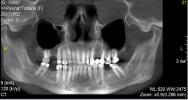

• CD-диск с КТ: от 09.12.2019.

• Конусно-лучевая компьютерная томография: от 20.01.2019 на 6 листах.

• Конусно-лучевая компьютерная томография челюстно-лицевой области: от 10.03.2021 на 1 листе.

• CD-диск КЛКТ: от 02.10.2017.

• CD-диск рентгенологического исследования: (именуемый по тексту документа как «Стоматологическая поликлиника № 9»).

• CD-диск КТ 16+16: от 04.03.2021.